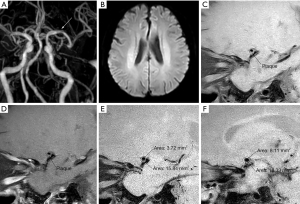

RI ≥1.05 was defined as PR (Figure 1); RI 0.96–1.04 was defined as non-remodelling; RI ≤0.95 was defined as NR (Figure 2). The plaque contrast enhancement grade was subjectively categorised as follows: grade 0—the enhancement was less than or equal to that of normal intracranial arterial walls in the same patient; grade 1—the enhancement was greater than that of normal intracranial arterial walls but less than that of the pituitary infundibulum; and grade 2—the enhancement was greater than or equal to that of the pituitary infundibulum (17).

In this study, patients with atherosclerotic MCA stenosis in the symptomatic group had a smaller LAMNL, larger PA, higher RI, more superior/posterior plaques, more obviously enhanced plaques, and a larger number of PR pattern than those in the asymptomatic group (Figure 2). Moreover, logistic regression analysis showed that the combination of PA, LAMNL, and the plaque enhancement degree had optimal predictive value for acute stroke. Our study also showed that HRMRI is a suitable method for depicting the features of vessel walls and plaques clearly without exposing patients to radiation injury, and it has extensive applications in intracranial artery diseases.